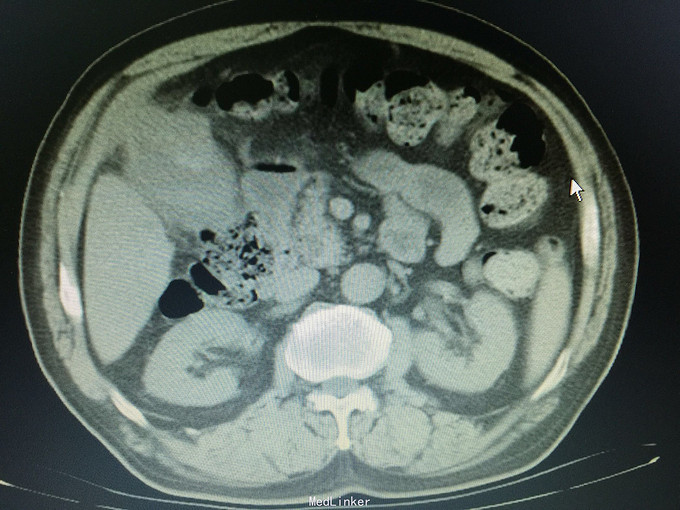

男,74岁 主诉:反复右上腹疼痛10年,再发并加重一天, 现病史:10年前开始反复右上腹疼痛,持续性绞痛,向同侧肩背部放散,曾经在当地医院以“胆囊结石”治疗,效果不佳,10年来反复发作,10小时前再次发作并疼痛难忍,来诊,无发热,无恶心、呕吐,尿色深,大便正常。

痛苦表情,皮肤及巩膜轻度黄染,腹部平坦,右上腹压痛,无肌紧张及反跳痛,未及包块,莫氏症阳性,肝区扣痛明显。 辅助检查:CT:胆囊轮廓欠清晰,密度不均,底部局限性增厚并向内突起,胆囊内见高密度影,胆总管扩张。

诊断:胆囊占位,胆囊结石,胆囊炎 处理:手术治疗,术中见大网膜与腹膜广泛粘连,胆囊质硬,与肝脏、12指肠及横结肠广泛粘连,与胃小弯及幽门部侵润致密。行胆囊癌根治术,胃破裂修补术,胆总管切开T形管引流,腹腔冲洗引流术。病理证实为胆囊中分化腺癌侵及浆膜层。(胆囊及胆总管内未见结石)